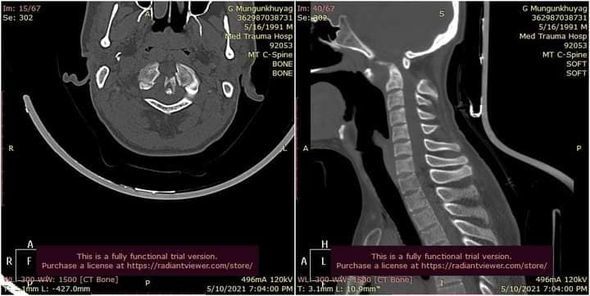

Гэмтэл Согог Судлалын Үндэсний Төвийн зөвлөх эмч Ж.Оюунтөгс, Л.Бат-Эрдэнэ тасгийн эрхлэгчтэй, Б.Баттөгс ахлагчтай Хүзүү Нурууны Гэмтэл Согогийн тасгийн хамт олон Монголд анх удаа хүзүүний нугалмын хугарал мултралыг арын хүрцээр дагз ястай хамт бэхлэх мэс заслыг амжилттай хийлээ.